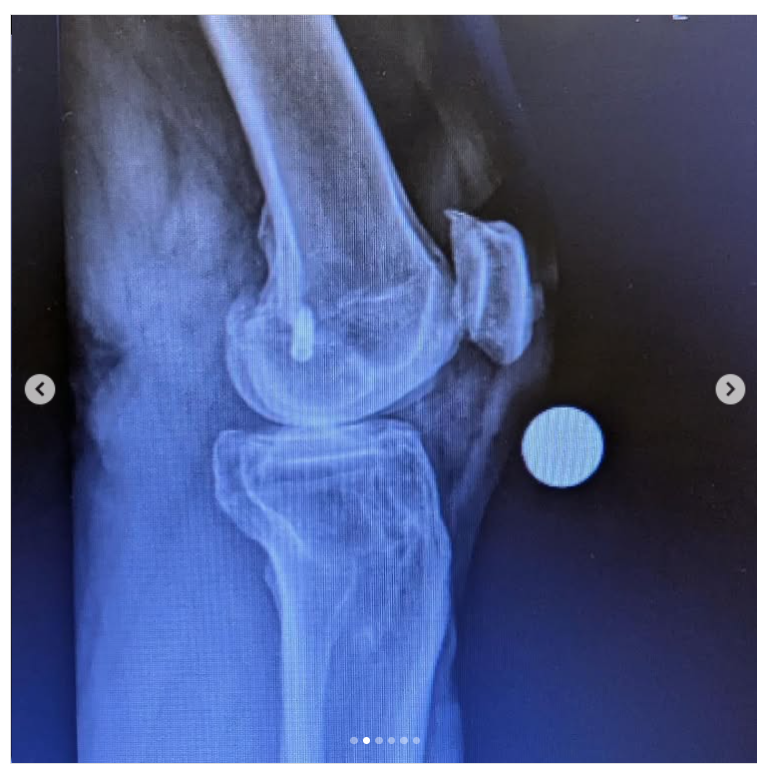

How it was. And how it is…

I am 7 weeks post op on a Total Knee Replacement. My left knee was on its last leg, and I have been putting this surgery off for years.

Post op X-Rays show everything is healing nicely.